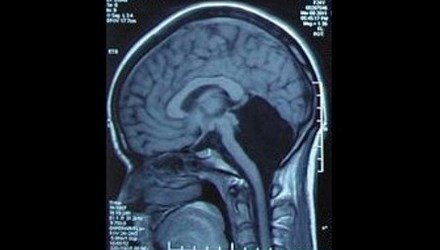

Cô gái đã lập gia đình và có một con gái. Các bác sỹ đã hết sức ngạc nhiên khi phát hiện cô không có tiểu não tức là thiếu một nửa não bộ mà vẫn có thể sống bình thường.

Một phụ nữ, 24 tuổi, ở tỉnh Quảng Đông, Trung Quốc phải nhập viện vì cảm thấy chóng mặt và buồn nôn. Sau khi chụp não, các bác sỹ của bệnh viện quân đội Quảng Đông hết sức ngạc nhiên khi phát hiện cô không có tiểu não (phần màu đen trong ảnh), tức là thiếu một nửa não bộ mà vẫn có thể sống bình thường.

Tiểu não nằm ở trung tâm hộp sọ, chứa khoảng một nửa số nơ ron thần kinh, khu vực chỉ huy việc cân bằng cơ thể, chạy nhảy, đá bóng và ngôn ngữ.

Do thiếu tiểu não nên đến 6 tuổi cô mới biết nói, 7 tuổi mới biết đi. Các cuộc kiểm tra cho thấy, cô có thể hiểu được các từ, nhưng gặp khó khăn khi phát âm, giọng của cô hơi run run và phát âm không được chuẩn.

Hiện cô đã có gia đình và có một con gái. Rất may cô bé có bộ não bình thường. Đây là một trong số 9 người trên thế giới mắc căn bệnh hiếm gặp này. Các bác sỹ tin rằng, các chức năng của tiểu não của cô có thể đã được thay thế bởi vỏ não.